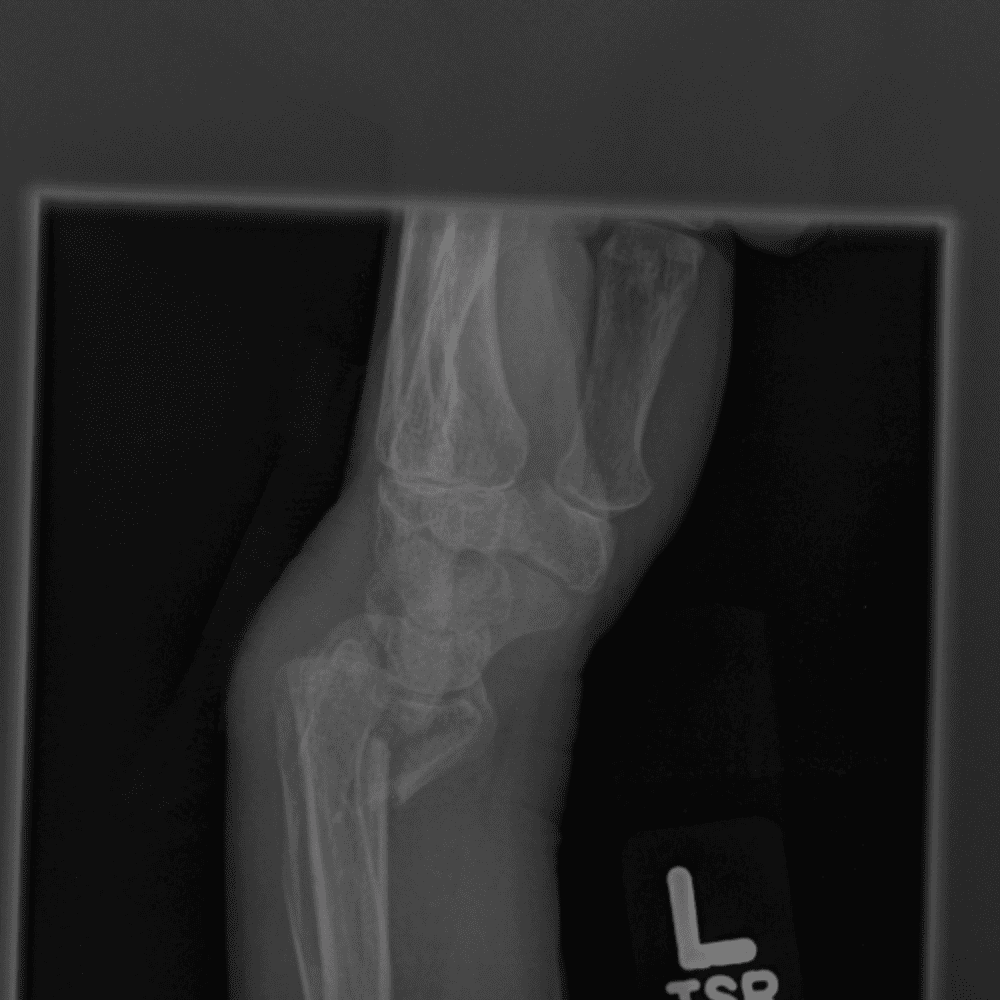

Simuliert den Dienst durch subtile oder schwierige Fälle und einige Normalbefunde.

30 Fälle